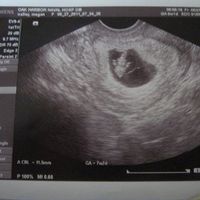

Just got our first ultrasound this morning!!!!

Mrs Cupcake, on May 27, 2011 at 5:46 PM

It was AMAZING to hear the baby heartbeat and see the little arms! I got little emotional and my husband got super excited lol. I am so grateful that he want to be a dad so badly since my father never...

Elizabeth, May 31, 2011 35